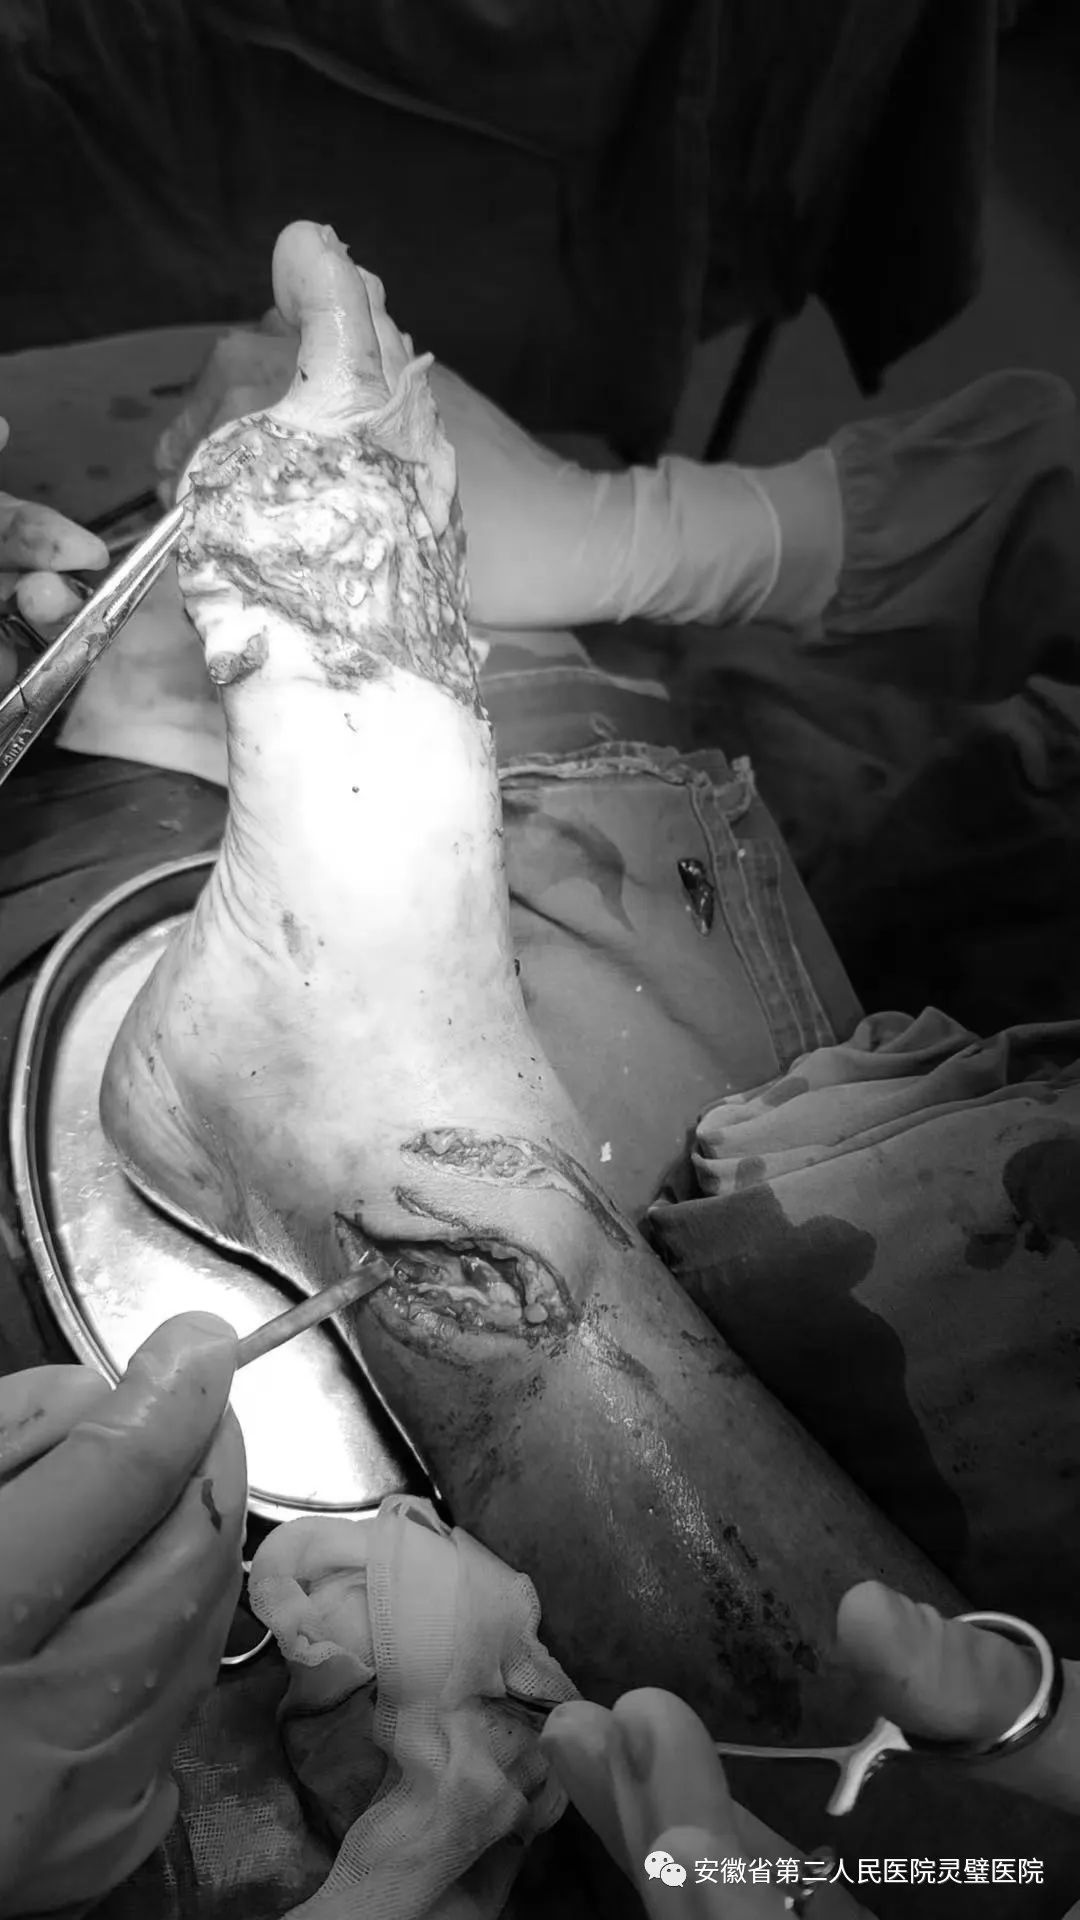

皮带搅伤致右足广泛脱套伤

患者男,73岁。在家干农活时不慎被皮带搅伤右小腿及足部,急诊手足外科检查创面较大,右小腿远端内侧可见斜形挫裂伤,周围皮肤碾压挫伤,创面污染,皮缘错灭,骨质外露。右足背广泛脱套,自足中部直至远端,皮肤挫伤明显,边缘血运欠佳,趾旋转挫裂,无血运,余四趾末梢血运欠佳。开通绿色通道,手足外科医生团队在麻醉、手术室全力配合下,为患者实施了撕脱皮肤原位回植+取皮植皮+KCI负压吸引术,手术过程顺利,术后恢复良好。